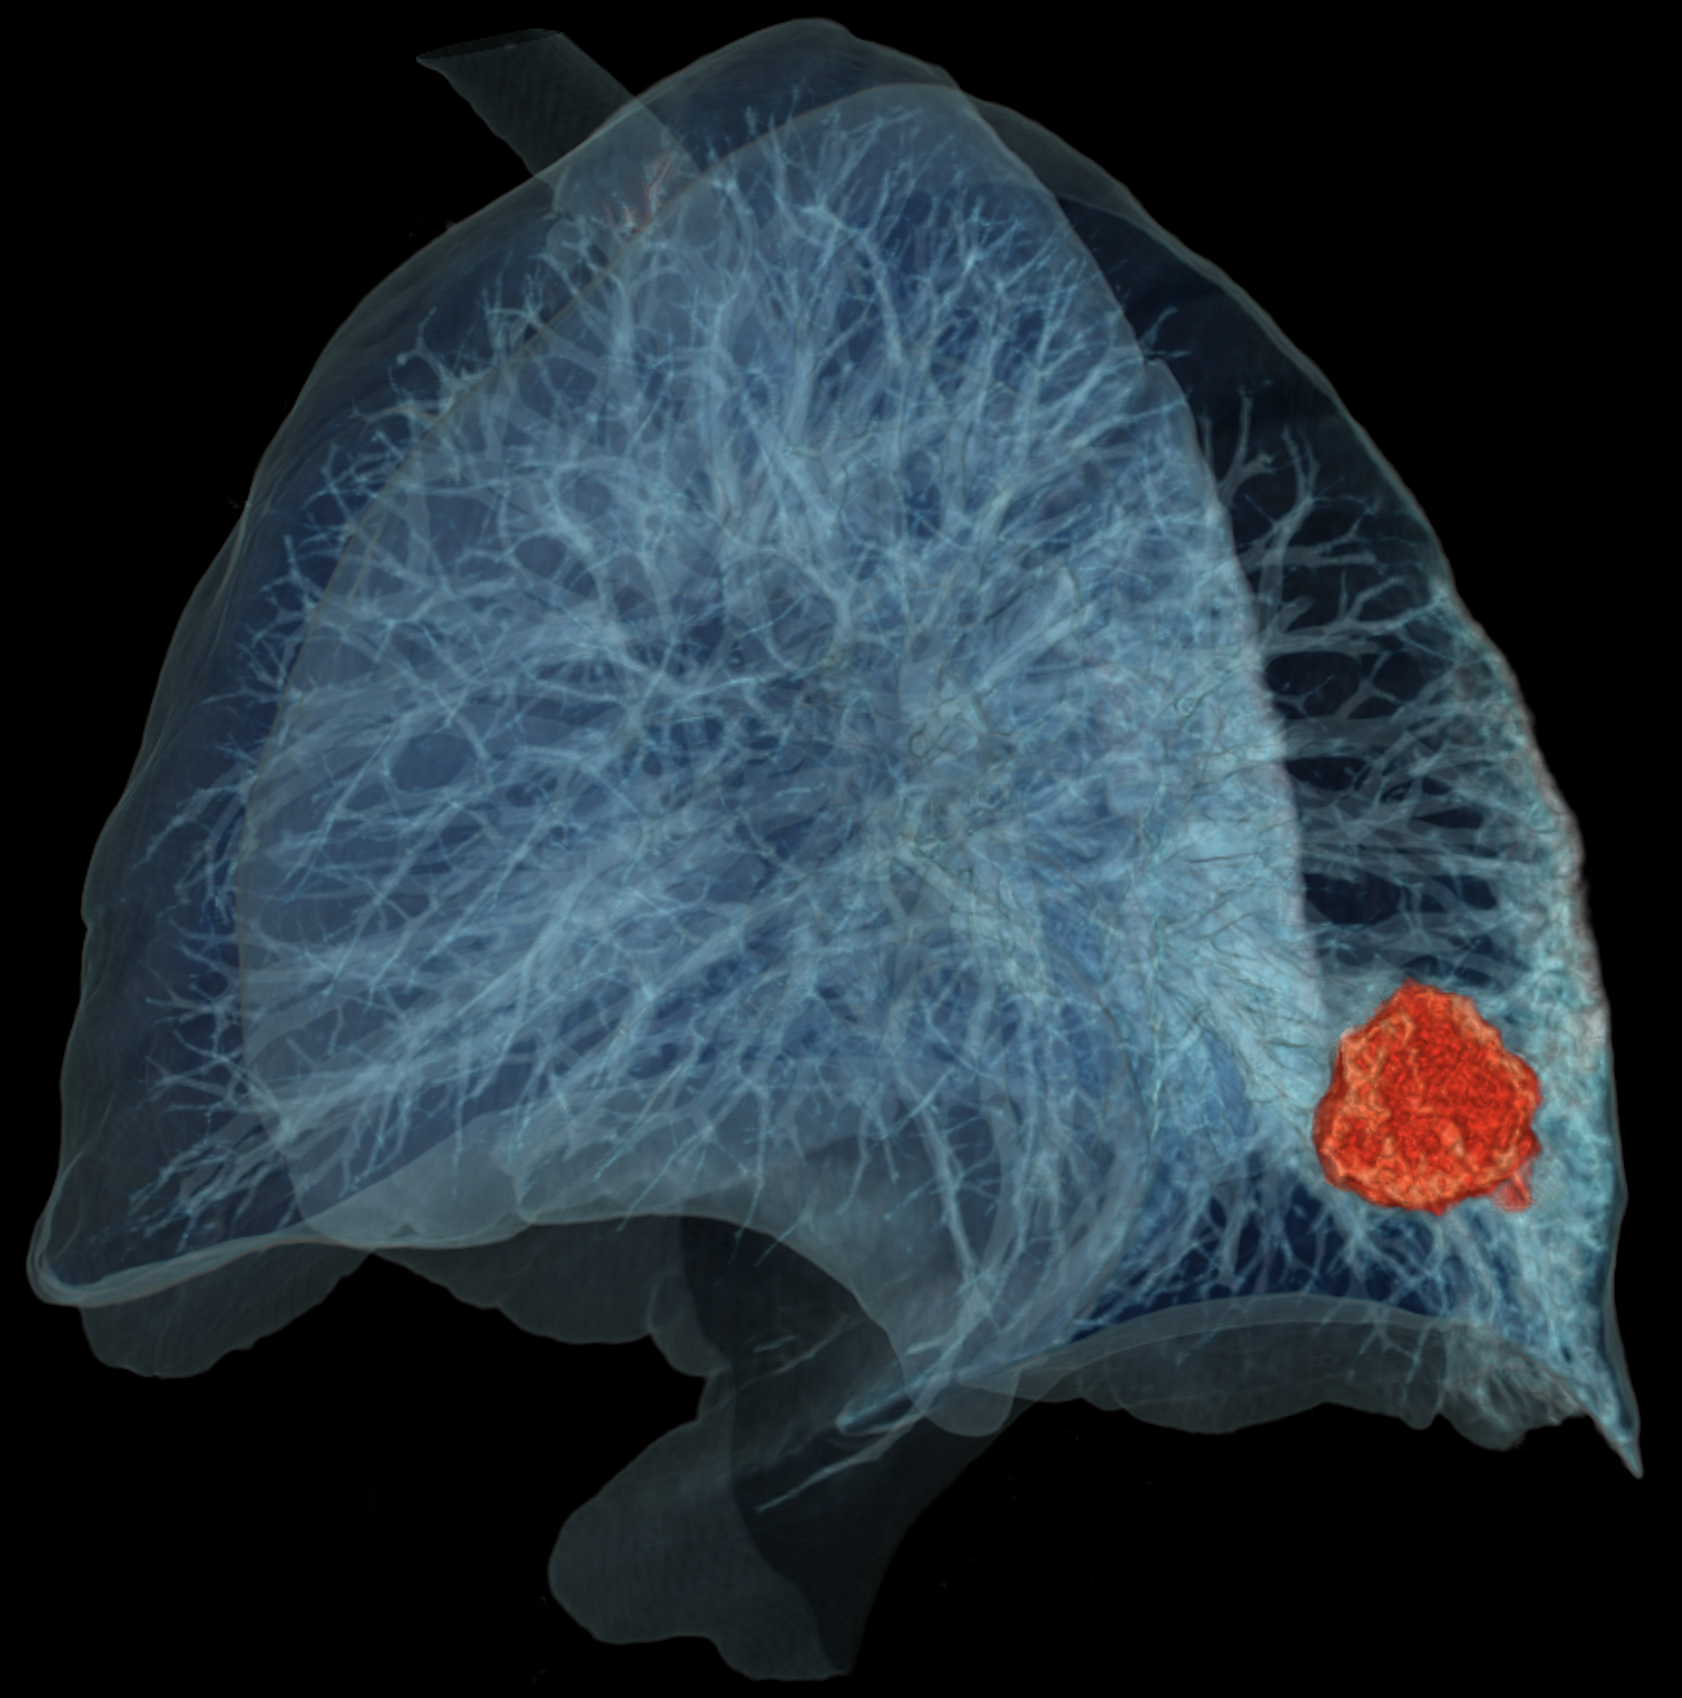

CD Lab MLPI

The CD Lab Machine Learning Driven Precision Imaging  (Start 2021) develops machine learning models for the prediciton of individual disease course and treatment response in lung cancer patients. It explores methodology, medicine and the legal aspects of using AI in clinical care. It is funded by the Christian Doppler Gesellschaft.